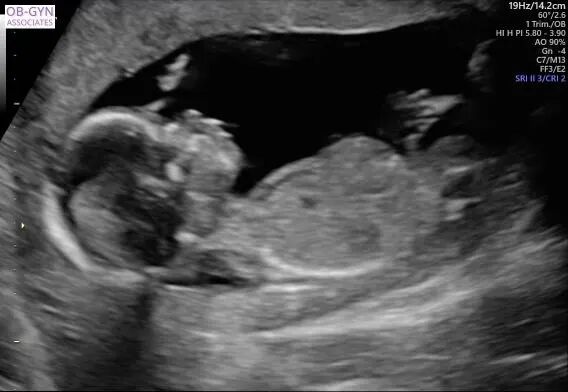

宝宝接近四个月的时候,爱妈Y再次进行了B超检查,此次检查清晰显示出一个健康可爱的女宝宝。爱妈随即将B超照片发送给准妈妈,并满心欢喜地赞叹宝宝的可爱。看到宝宝健康成长,准妈妈既感动又高兴,对爱妈的细心照料表示深深的感激。 准父母成功匹配后,我们会为双方建立一个交流群,这样准父母和爱妈可以方便地进行沟通。在这个群里,爱妈和我们的客服团队会定期更新检查结果和宝宝的成长情况。我们都非常期待下次见到宝宝的时刻!